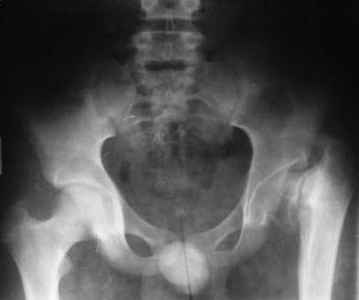

Больному 16 лет, болеет с рождения.Оперирован в детстве( корригируюшая межвертельная остеотомия с фиксацией пластиной), три года назад удалии пластину. Обратился к нам, выраженно хромота, укорочение бедра на 4 см, ходит безболезненно, отведение ограниченно при отведении и ротации. Буду рад вашим предложениям. С уважением Шухрат!

То, что Вы показали это не дисплазия, это врожденная COXA VARA.

Проблема не только в малом ШДУ, необходимо изменить наклон опорной площадки вертлужной впадины. Деваризирующая межвертельная остеотомия без полной коррекции (менее 130 градусов)+ периацетабулярная остеотомия. Без второго этапа перегрузка верхнелатерального отдела сохранит условия для этой формы артроза.

1.D-s: Coxa vara, colly lysis,(дистрофическая Coxa vara)

2. Рентгенография левого тазобедренного сустава в положении максимального приведения бедра: если головка занимает позицию 130 градусной инклиниции (имитация положения головки при нормализации ШДУ) то, или межвертельная по Пауелсу (проще), или подвертельная с латерализацией дистального фрагмента (для относительного удлинения шейки) (подвертельная без латерализации усилит имеющийся вальгус в колене)

Если 130 градусная иклинация невозможна (нет 60 градусов приведения) тогда операция SUPER (standart utilitarian procedure extremity reconstruction) hip по Droor Paley.

3. Выполнение периацетабулярной остеотомии дискутабельное: соотношение головка-впадина несферическая инконгруентность, хотя возможно через 3-6 месяцев вторым этапом с osteochondroplasty. Одномоментно невозможно из-за большого давления головки на впадину.